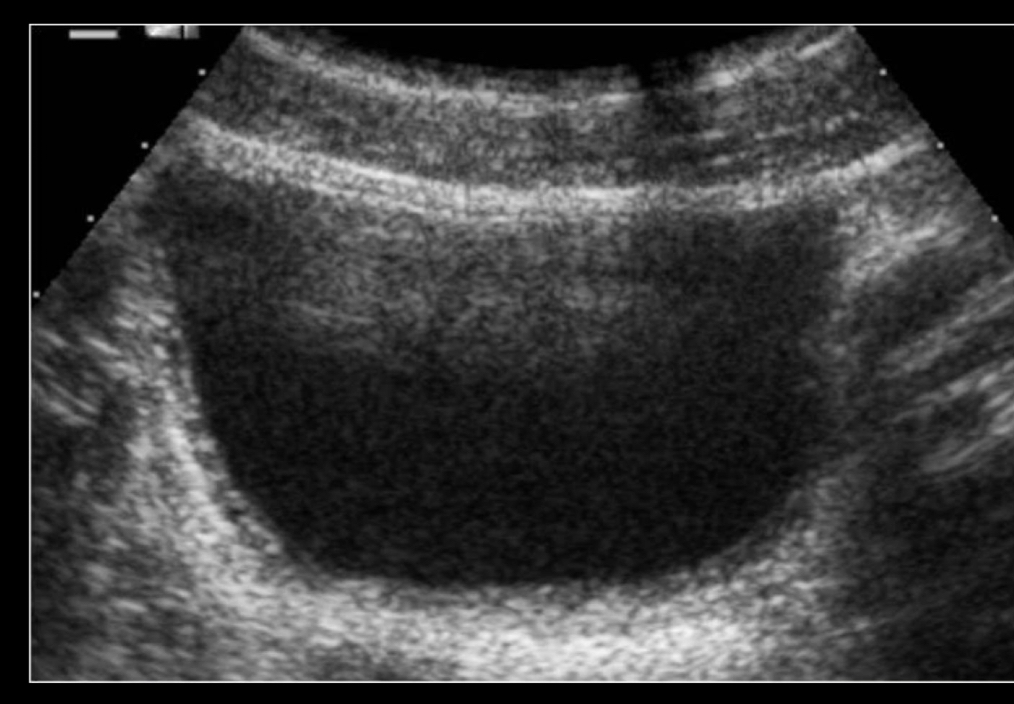

q se ve en US de la cistitis

A

• siempre con vejiga llena

• Paredes engrosadas

• Orina turbia

• Se ve ecos puntiformes: sedimiento urinario